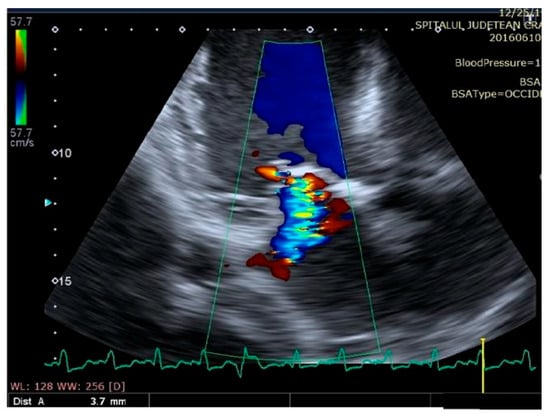

Some echocardiographic aspects revealed in the transthoracic echocardiographic examination before and after CRT are presented in Figure 3, Figure 4, Figure 5, Figure 6, Figure 7, Figure 8 and Figure 9.

Figure 6.

Mitral regurgitation (highlighted as multicolored mosaic pattern, green and yellow), before therapy with a cardiac resynchronization device.

Figure 7.

Mitral regurgitation (highlighted as multicolored mosaic pattern, green and yellow), after therapy with a cardiac resynchronization device.